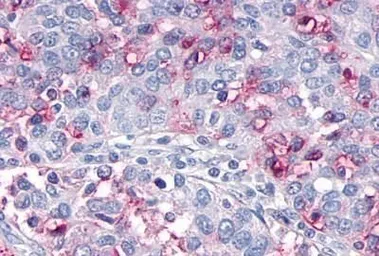

OR10R2 antibody

Cat. No. GTX71527

ApplicationsIHC-P

ReactivityHuman, Rabbit, Bovine, Monkey